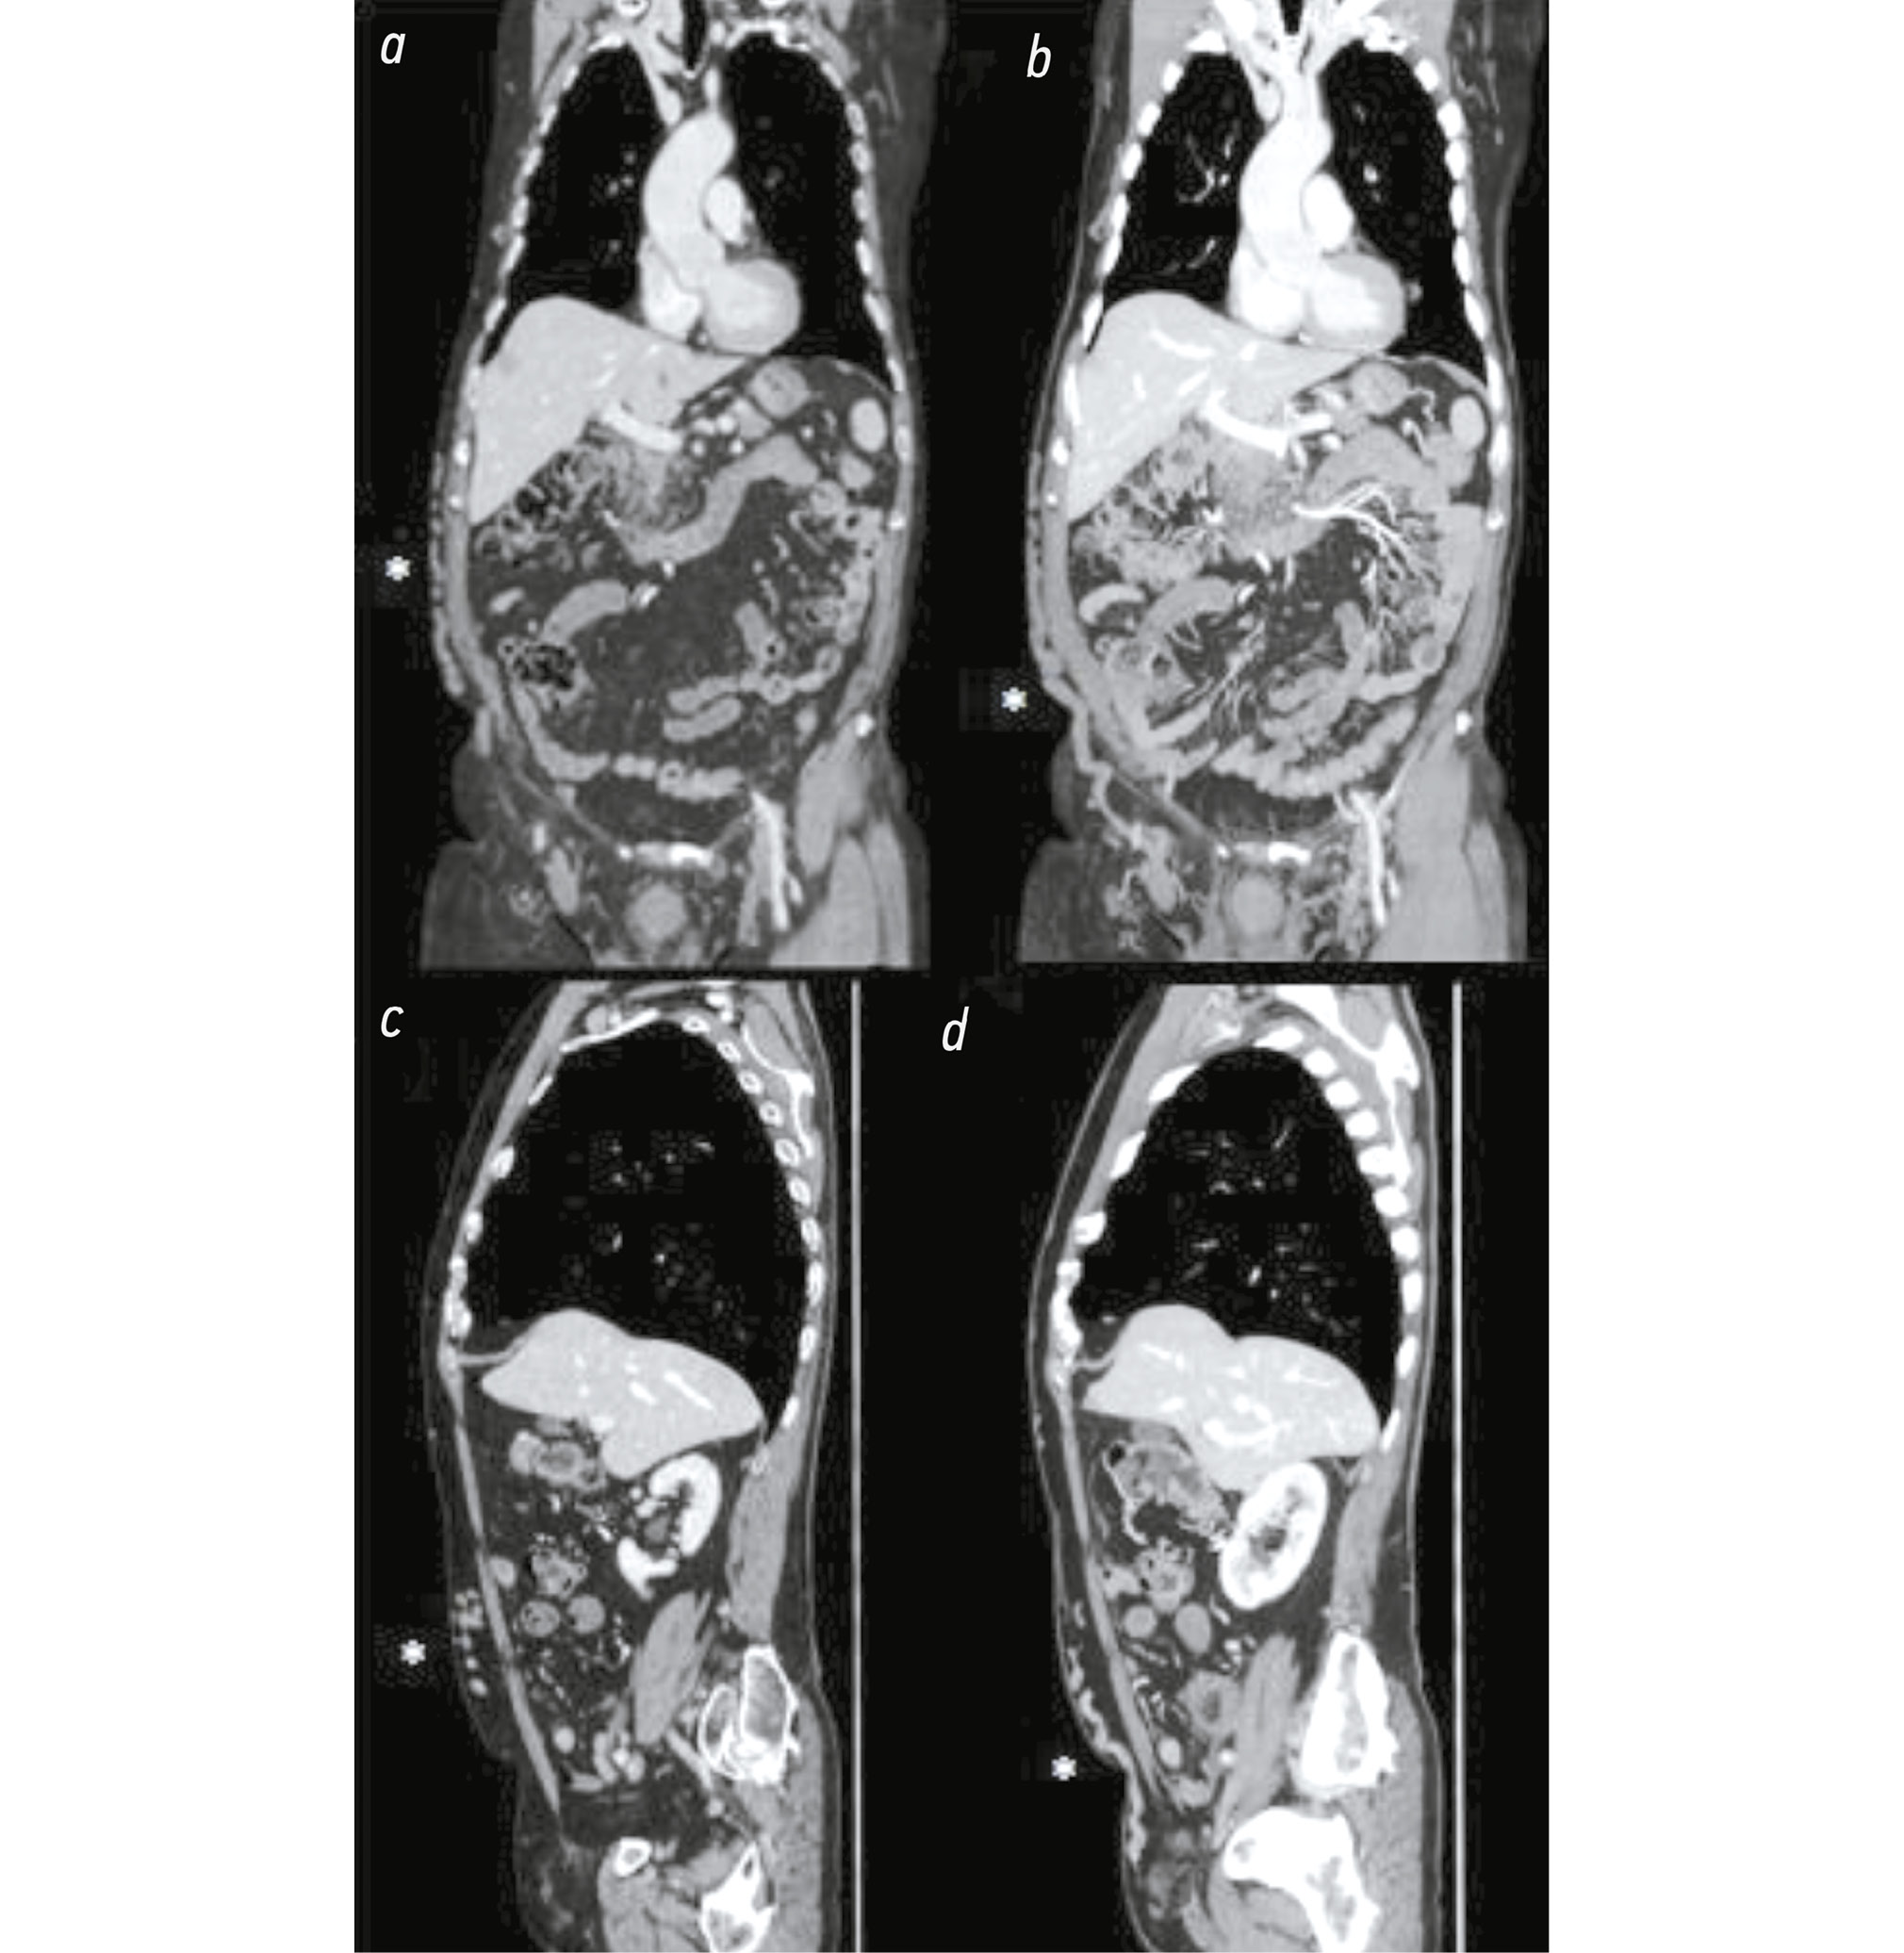

The patient was not aware of this variant in the vascular anatomy and had never had symptoms related to it (Fig. 1).

Fig. 1. Computed tomography images of the axial section of the abdomen (portal phase): a) The small suprarenal IVC is indicated by a yellow asterisk. b) Lower in the abdomen, the yellow asterisk indicates the hypoplastic IVC, and the hypertrophic collateral venous circles in the anterior abdomen wall on the right are indicated by a white asterisk. c) Another lower axial section showing the small IVC (yellow asterisk). d) The drainage on the right side is accomplished by a constant iliac vessel (yellow asterisk).